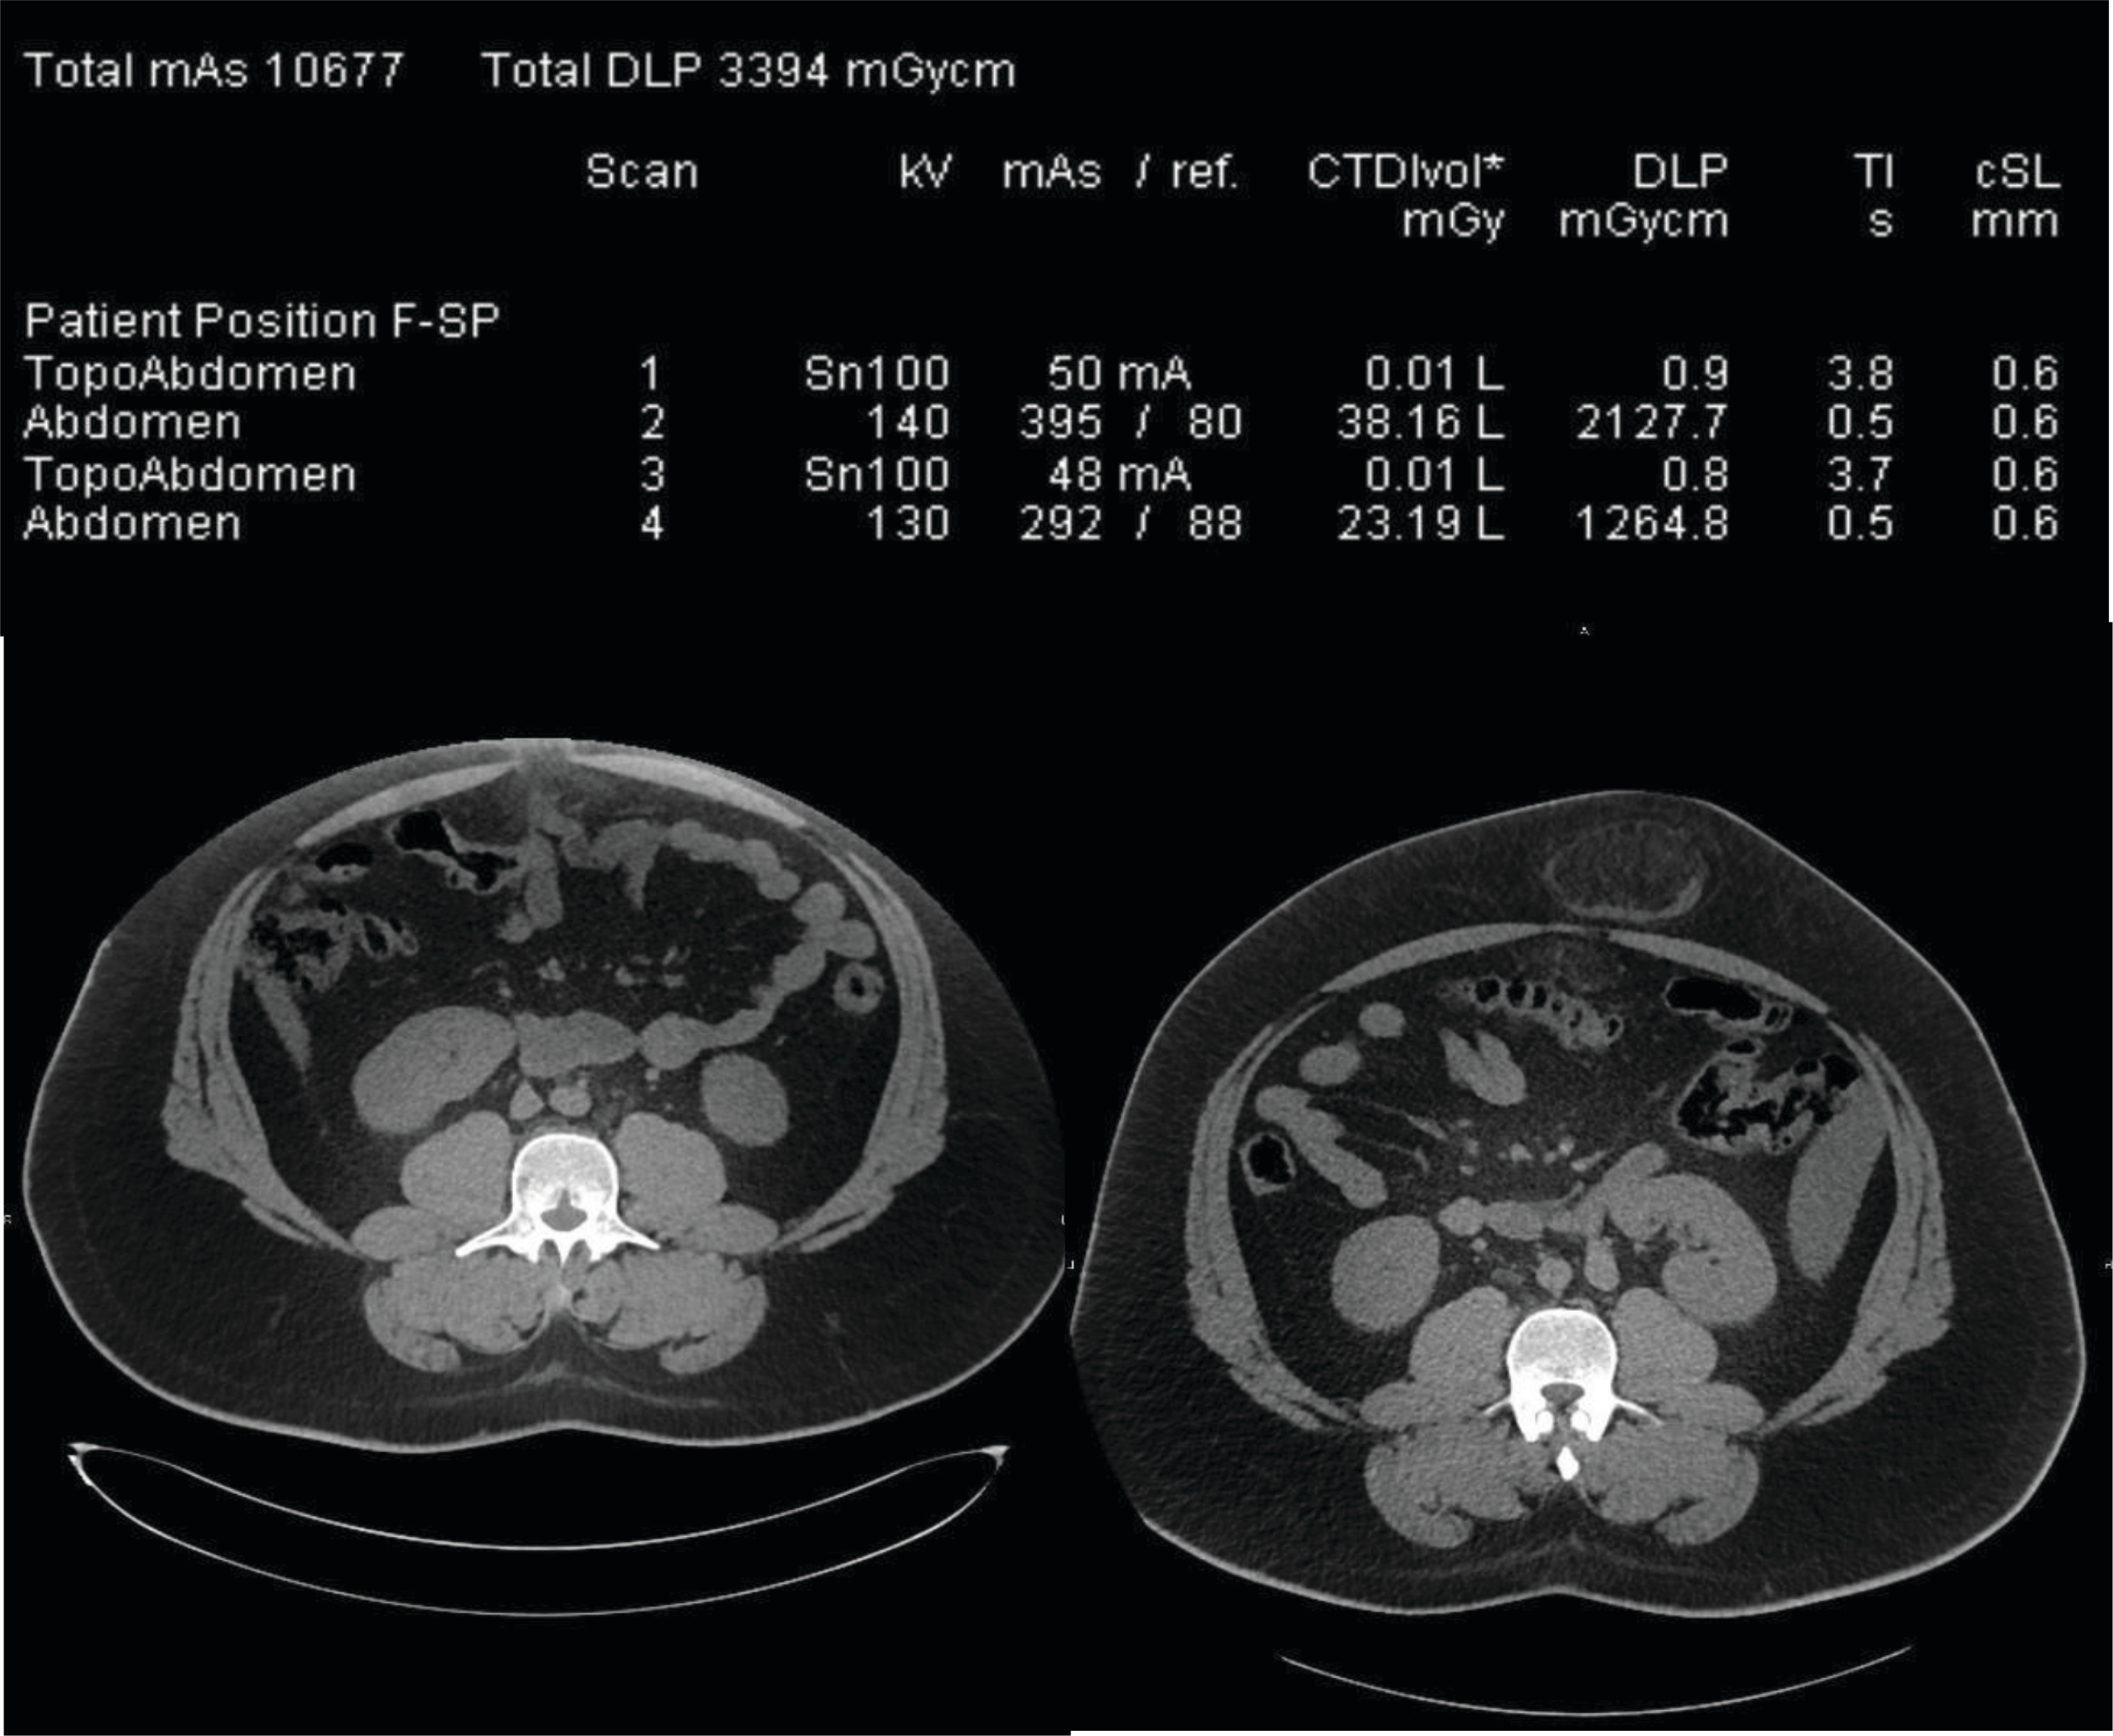

Figure 1

Radiation dose report and CT slices obtained at the level of the umbilic in a 24 year‑old patient. The left CT slice is off‑centered and the herniation is not visible whereby the right CT slice of correctly centered and the herniation is visible. The two first exposures on the dose report correspond to the left image whereby the two last lines correspond to the right image including the umbilical herniation.